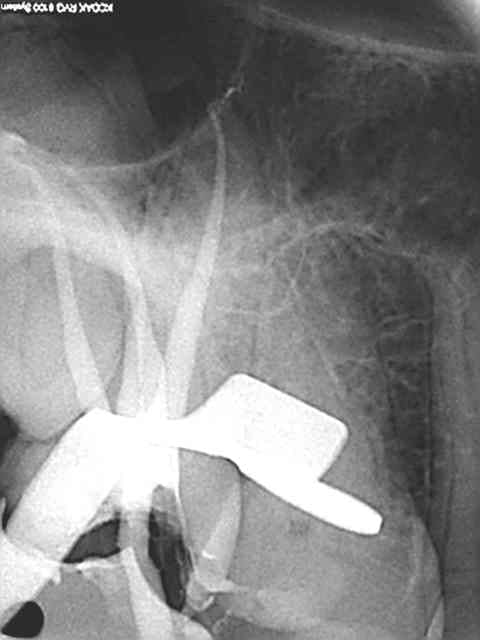

Faudrait que je la retrouve mais y'a une vidéo avec une radio qui m'a fait mal dans mon ego...

Sinon, pour répondre à la question, j'utilise un seul cône calibré Protaper, je descend avec le MacSpadden jusqu'à 5mm de l'apex sur CA bleu plein pot et ça tasse en 5 secondes (pas plus longtemps sinon ça chauffe, pas plus bas sinon ça fuse). Les astuces: un coup d'air pour dégager l'excès de ciment à l'entrée du canal avant introduction de l'instrument (le ciment fait tampon à la chaleur et gêne la fusion du cône), si ça ne suffit pas --> instrument de plus gros diamètre (il existe des sets pas chers avec des diamètres jusque 80, ça dépanne parfois sur un gros canal palatin ou après une dépose de tenon).